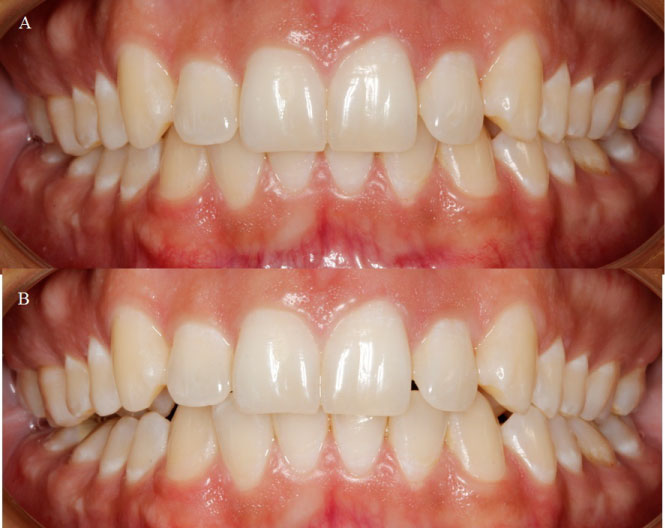

Figure 2: A) Intraoral photography showing maximum intercuspation; B) Intraoral photography showing maximum mouth opening. View Figure 2